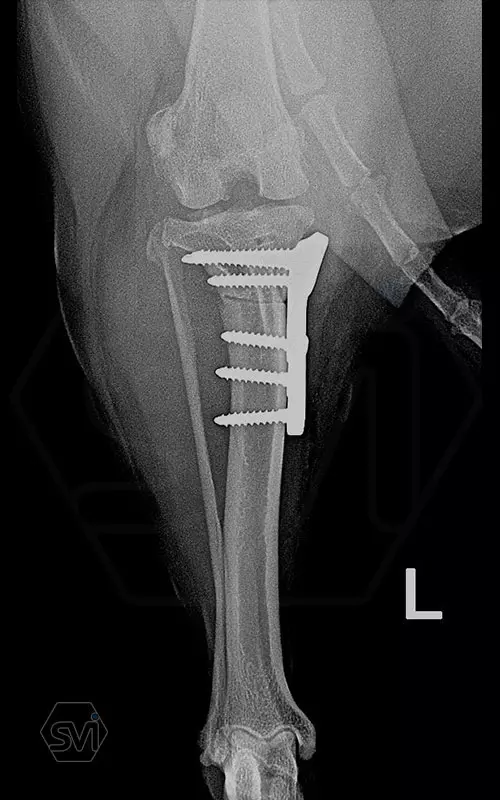

The cranial cruciate ligament rupture of a 7-year-old 8 kg active mix dog was solved a year ago with a precontured polyaxial 2.4mm system, now the other leg has been laid out, and this plate was used here as well. The stability of the system, its fit to the bone and the good healing can be measured nicely on the 1-year control X-ray.

The 2.4 system is great to use where the 2.0mm is already small, but the 2.7mm is still very big. This is a populous family of 6-14 kg dogs, according to our own data for 2021, the 2.4 mm size makes up 14% of all TPLO surgeries!